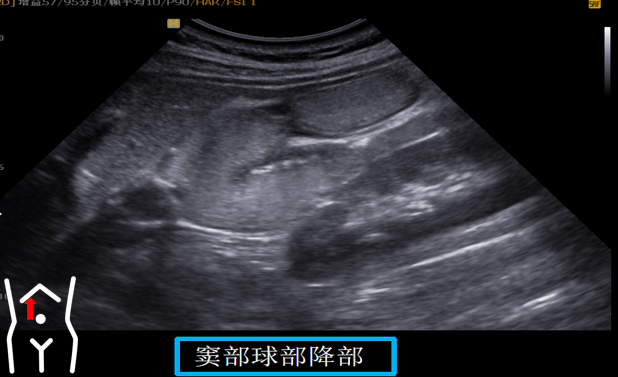

患者从右卧位改成平卧此时头也随着患者改变体位而由横切改为纵切在脐孔与右肋缘连线处扫出胃窦幽门管幽门孔球部降部水平部